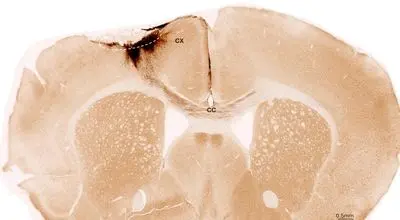

درمان با سلولهای بنیادی توانست آسیبهای ناشی از سکته مغزی را در موشها معکوس…